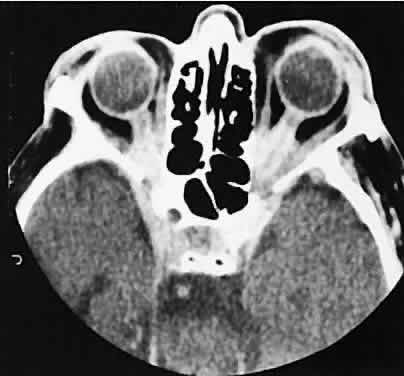

Lacrimal fossa lesions deserve separate consideration and do not fit any other convenient classification scheme. The lacrimal gland is a substrate for various tumors both benign and malignant. Benign lesions are typified by the pleomorphic adenoma (benign mixed tumor). The clinical profile of painless progressive proptosis is matched with a CT picture that shows an enlarged, sometimes nodular, well-delineated lacrimal gland (Fig. 16). Bone windows may show pressure expansion and thinning of the bone in the lacrimal fossa. Intralesional calcium61 or intralesional hemorrhage62 also may be present.

Fig. 16. Benign mixed tumor of the lacrimal gland. Axial (A) and coronal (B) views show a well-demarcated hyperdense mass that expands the fossa of the lacrimal gland by pressure effects rather than erosion. Suggestion of mixed density is apparent on the axial view, and globe displacement is evident on the coronal view.